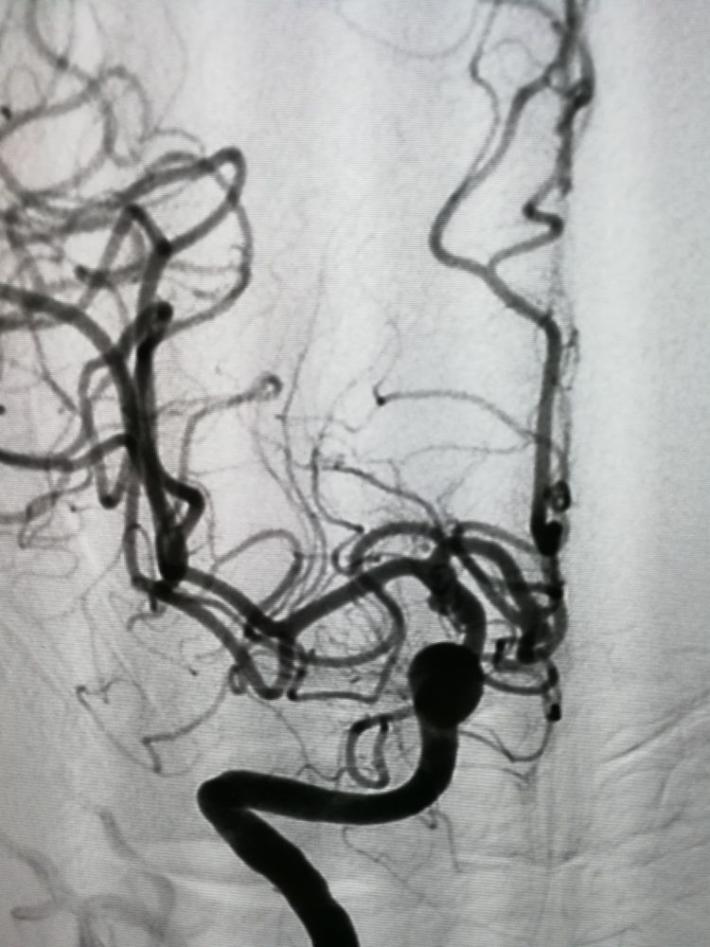

发病后6天(入院当天)DSA示:右侧前交通动脉瘤,右侧脉络膜前动脉瘤,仔细阅片,认为责任动脉瘤为前交通动脉瘤可能性大。原因如下:前交通动脉瘤约2x3mm大小,形状较狭长,瘤顶指向右侧前下方(也可解释蛛血部位)。而脉络膜前动脉瘤约1×1mm大小,形状较扁平,破裂可能性相对小些。

拟行介入栓塞术,术前(发病一周)再造影,前交通动脉瘤“消失了”!

以原造影3D为依据,选择一角度再造影,见动脉瘤“若隐若现”,但路图上动脉瘤仍不显影,仔细观察血管,见同侧A1、回返动脉较前一日痉挛,分析系此因素加上动脉瘤小且窄颈的原因导致造影剂进入动脉瘤内太少,以致动脉瘤显影不良。考虑瘤体很小,路图上又不显示,盲目栓塞风险很大,决定终止手术,改行开颅夹闭。